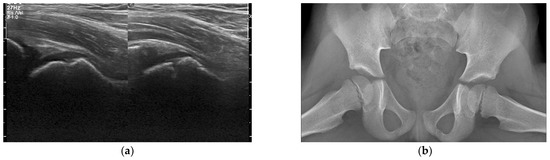

3.3. Radiologic Investigations

- Trusen, A.; Beissert, M.; Schultz, G.; Chittka, B.; Darge, K. Ultrasound and MRI features of pyomyositis in children. Eur. Radiol. 2003, 13, 1050–1055. [Google Scholar] [CrossRef]